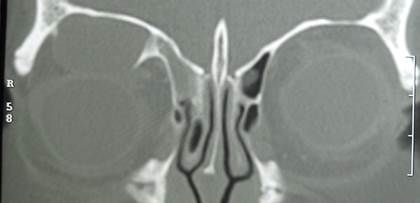

Enfermedad distiroidea de la órbita

La enfermedad de Graves u oftalmopatia tiroidea es una enfermedad autoinmune que afecta principalmente a pacientes femeninos jóvenes generando inflamación y expansión de la grasa orbitaria y desplazamiento ocular subsecuente (proptosis) aunque sus manifestaciones pueden ser múltiples incluyendo ojo rojo, lagrimeo, sensación de basura, fotofobia, dolor, visión doble e inclusive ceguera (más frecuentemente en pacientes arriba de la quinta década de la vida). Si bien la oftalmopatía suele estar precedida por un cuadro de hipertiroidismo, es frecuente observar diversos estados tiroideos en los pacientes. Algunos de los factores de riesgo más importantes para el desarrollo y progresión de esta enfermedad son el tabaquismo y el uso de yodo radioactivo. Su diagnóstico es clínico corroborándose con diversos estudios como pruebas de función tiroidea con anticuerpos, tomografía computada y campo visual.

Su tratamiento depende del grado de afección (severidad) y actividad inflamatoria. Los esteroides sistémicos y lubricantes oculares representan una opción eficaz aunque los anticuerpos monoclonales empiezan a posicionarse entre las opciones terapéuticas más novedosas . El manejo multidisciplinario entre oftalmólogo, endocrinólogo y reumatólogo representa la mejor forma de evitar complicaciones graves asegurando una resolución de la enfermedad más rápida y con menos secuelas.